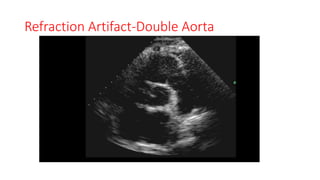

Refraction Artifact

• A refraction artifact, also called a ‘‘lens artifact,’’ is the false duplication of

an object behind a structure that acts as a wave refractor and thus behaves

as a lens.

• Ultrasound waves directed through the ‘‘lens’’ are refracted toward the

respective cardiac object and then rerefracted back to the original direction

of transmission on the return acoustic path, resulting in a duplicate image

of this object but in the original direction of the beam.

• These artifacts occur mostly in subcostal and parasternal imaging planes,

with costal cartilage, fascial structures and fat, and pleural and pericardial

surfaces acting as the medium inducing refraction of the ultrasound beam

RefractionArtifacts

Refraction Artifact-Double Aorta

Refraction Artifact • Arefraction artifact, also called a ‘‘lens artifact,’’ is the false duplication of an object behind a structure that acts as a wave refractor and thus behaves as a lens. • Ultrasound waves directed through the ‘‘lens’’ are refracted toward the respective cardiac object and then rerefracted back to the original direction of transmission on the return acoustic path, resulting in a duplicate image of this object but in the original direction of the beam. • These artifacts occur mostly in subcostal and parasternal imaging planes, with costal cartilage, fascial structures and fat, and pleural and pericardial surfaces acting as the medium inducing refraction of the ultrasound beam

• 28.

• 29.